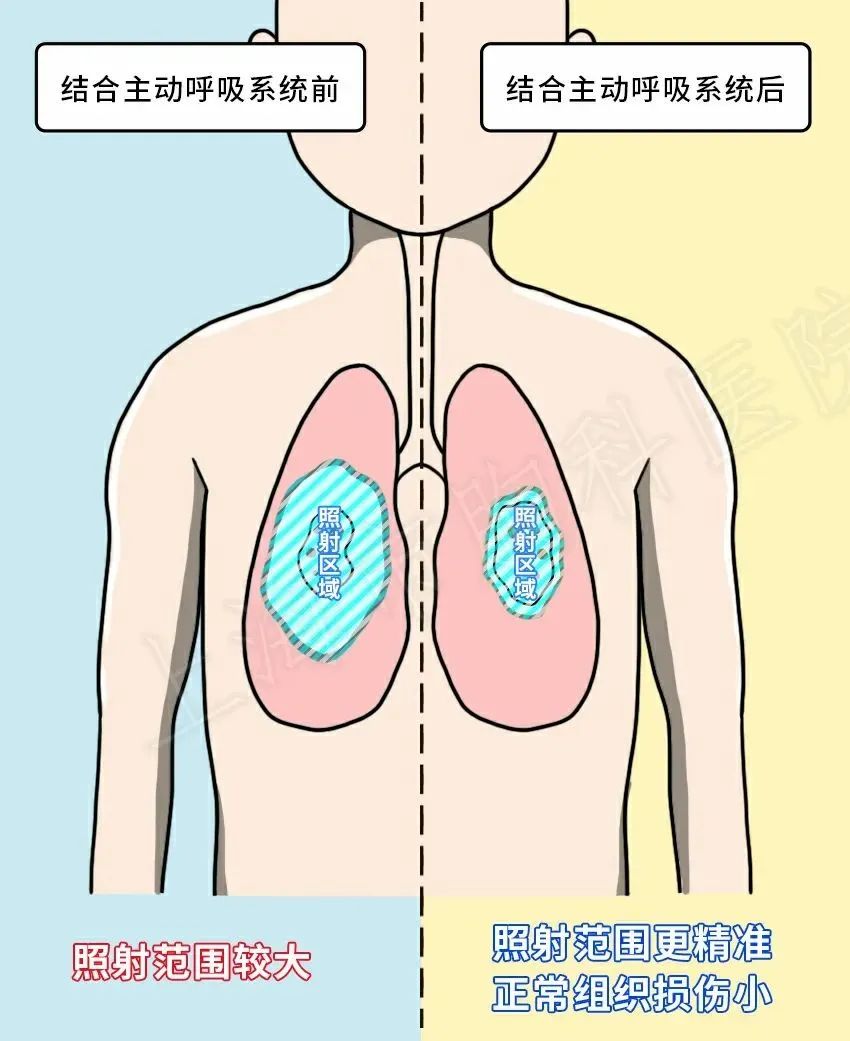

“节拍治疗适用于三代EGFR-TKI治疗后无症状缓慢进展的患者,双倍剂量伏美替尼适合于肿瘤还依赖EGFR信号通路的无症状缓慢进展或全身控制良好的脑转移复发患者。”何志勇主任解释道。另外,三代EGFR-TKI联合抗血管靶向药物、或联合局部放疗,也是团队长期在临床探索的有效的治疗策略。